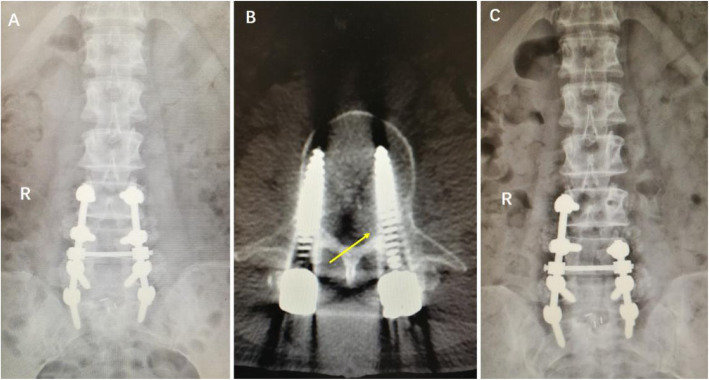

A 62-year-old female experienced pain in the front of her left thigh and had grade 1 hip flexion muscle strength 3 days after an L3–S1 PLIF. a Postoperative x-ray. b CT scan showed that the left L3 pedicle screw intruded the inner pedicle wall (arrow). c The left L3 pedicle screw was removed after reoperation. The patient’s symptoms were relieved after reoperation

Fig. 3.

A 44-year-old male experienced numbness in his left dorso-phalangeal toe and had dorsiflexion and grade 2 muscle strength in his left ankle 1 day after an L4/5 discectomy and an L3–5 PLF. a CT scan showed that the left L4 pedicle screw had entered the spinal canal. b X-ray after the left L4 pedicle screw was adjusted during surgery. The patient’s symptoms (numbness, weakness) were relieved after reoperation